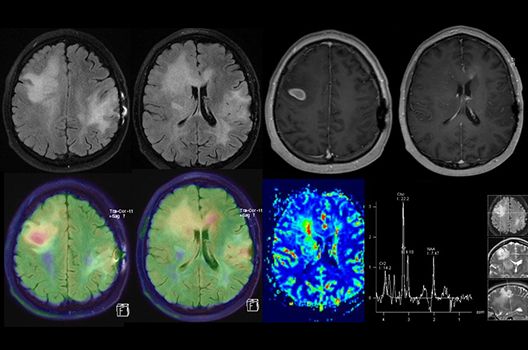

- MR-Protonenspektroskopie

- Funktionelle Bildgebung des Gehirns (fMRT)

Die Schwerpunkte in der MR-Forschung liegen in der multiparametrischen und funktionellen Bildgebung bei onkologischen und anderen, neuroradiologischen Fragestellungen und umfassen die Anwendung modernster MR-Verfahren sowie die Untersuchung an Hochfeld-Geräten.

Die Magnetresonanztomographie (MRT) ist ein Verfahren, bei dem durch magnetische Kräfte Bilder des Körperinneren angefertigt werden. In der Neuroradiologie können manchmal kleinste Veränderungen schwere Folgen haben; daher forschen wir an der Entwicklung hochauflösender MRT-Sequenzen, mit denen diese Prozesse und auch einzelne Nervenfaserbahnen sichtbar gemacht werden können. Darüber hinaus sind bei vielen Erkrankungen des Gehirns die Blutgefäße betroffen. Daher arbeiten wir an der Neu- und Weiterentwicklung von MRT-Sequenzen zur Darstellung der Blutgefäße und zur Blutflussanalyse (sog. „Angio-MRT“). Einen besonderen Forschungsschwerpunkt unserer Klinik stellen die MR-Protonenspektroskopie und die funktionelle MRT dar, mit denen die Analyse einzelner chemischer Substanzen im Hirngewebe oder die Darstellung ausgewählter Hirnfunktionen möglich ist.